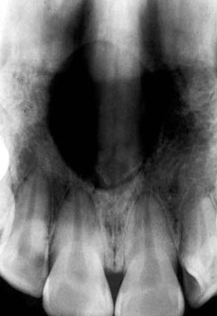

Consideratii radiografice. Se evidentiaza o radiotransparenta de 1-2cm si mai rar de pana la 6 cm. Este bine delimitata, situata intre radacinile incisivilor centrali superiori, pe linia mediana sau imediat paramedian, fara a avea punctul de plecare de la nivel periapical. Radacinile acestor dinti sunt divergente si rareori cu fenomene de resorbtie radiculara. Imaginea radiografica este de "inima de carte de joc".

Fig.34 Radiotransparenta in forma de "inima de carte de joc"

ce corespunde unui chist nazo-palatin.

Diagnostic diferential. Uneori, in mijlocul acestei zone de radiotransparenta se poate proiecta spina nazala anterio-inferioara putand da nastere la confuzii in sensul presupunerii a doua chisturi radiculare pe ambii incisivi.